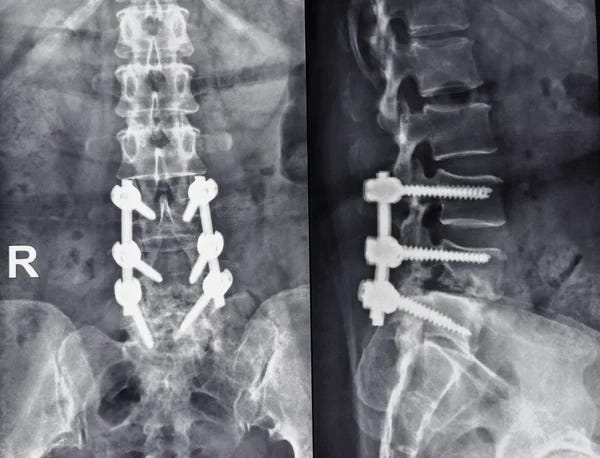

The Suspect’s appeal at this point is that he’s not insane. Although I would never do anything like that, his actions are logical to a certain degree. That, and magnified by his victim being part of an organization that has caused harm and misery, is also noted because it seems a lot of people have the desire to do the same action, but they don’t. But the Suspect did do it, and not only that, but he’s handsome. He has become or is a perfect package with intelligence, upbringing, and part of the academic world. There is also a theory that he suffers from Spondylolisthesis, which is a physical condition that affects the spinal and, therefore, causes or contributes to severe pain in his body, especially the back.

Pain or even the fear of pain can cause reactionary gestures. In a proper society, pain would be treated in a manner that would be helpful to the patient and, in turn, improve the world. Yet, some (such as health insurance companies) contribute to the misery of the sick as they suffer, making the patient and family feel like they are caught in a web they cannot crawl out of or the feeling of being in quicksand and those who can help simply ignore them. In dark times, it makes sense that it is not lightness but another version of darkness that comments on the world we are stuck in.